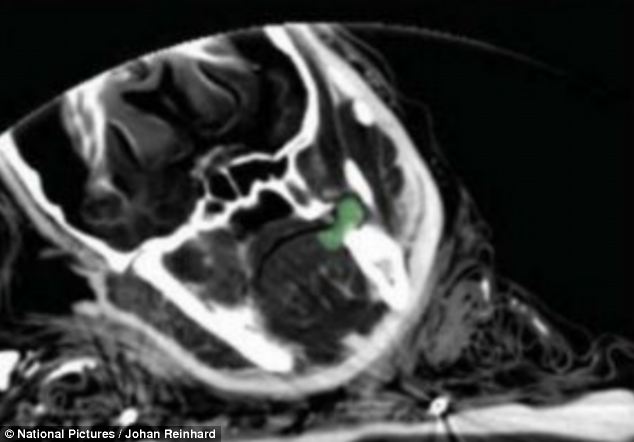

Known as the Ice Maiden, she is one of three children found in stone tombs on a mountain in Argentina.

The girl, the eldest of the three, was found cross-legged, with her head slumped forward and her hands resting in her lap.

She wore a feather headdress over her tightly braided hair and there were coca leaves between her teeth and balled up behind her cheek.